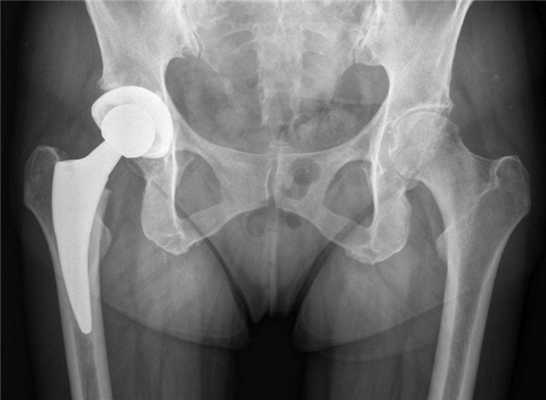

Некоторые люди считают, что МРТ нельзя делать при наличии металлических иплантатов, штифтов и накостных пластин. Однако это заблуждение. Большинство современных металлоконструкций изготавливают из сплавов, которые не разогреваются и не смещаются в магнитном поле.

МРТ следует проводить с большой осторожностью в тех случаях, когда в теле человека есть несколько металлических имплантатов больших размеров. При этом в ходе исследования врачи должны использовать дополнительные меры предосторожности. К примеру, они могут дать в руку пациенту специальную кнопку. Если тот почувствует жжение или дискомфорт, то сможет сразу же оповестить об этом медработников.